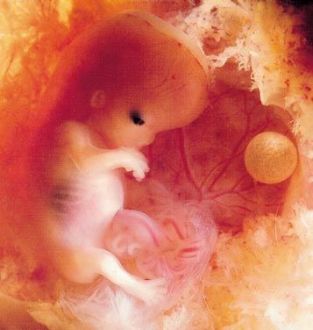

6 SG / 8 SA

Votre grossesse avance et Bébé continue de pousser. Dès cette semaine 6 de grossesse, ses membres s'allongent et ses yeux se recouvrent d'une membrane qui deviendra plus tard ses paupières.

6 semaines de grossesse : où en est bébé ?

Durant cette 6e semaine de grossesse, l’embryon mesure 1.7 cm et pèse 1.5 g, il a donc doublé sa taille en une semaine. Il est toujours replié sur lui-même et sa tête est penchée en avant. Sa tête est beaucoup plus grosse que le reste de son corps, son front est toujours bombé et son nez est aplati.

Dès cette 6e semaine de grossesse, sa bouche est épaisse et commence à se développer : les germes des dents de lait apparaissent et on discerne sa langue. Ses yeux immenses se sont rapprochés et sont recouverts d’une membrane qui deviendra par la suite ses paupières.

Durant la semaine 6 de grossesse, les membres de son corps s’allongent et on devine les articulations des coudes et des genoux. Quant à ses mains et ses pieds, ils ont des doigts palmés. Même si cela est encore imperceptible, Bébé bouge maintenant dans votre ventre. Toute la croissance de votre futur bébé se joue au cours du premier trimestre de votre grossesse.